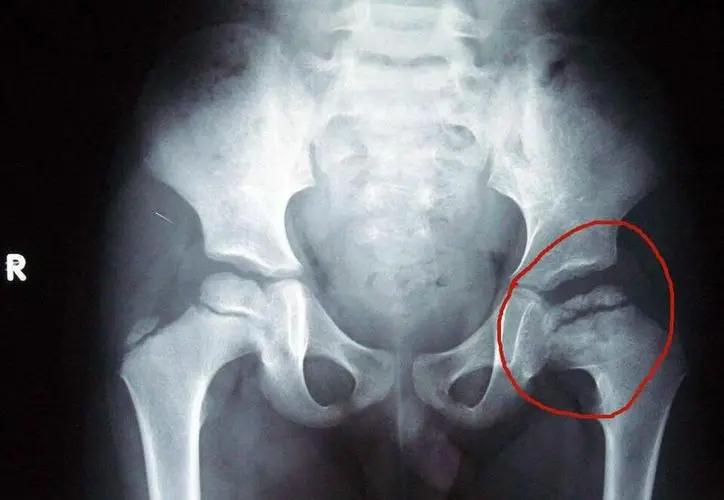

三氧及其产生的多种强氧化物质能溶解关节腔内的蛋白多糖,使关节增生性病变萎缩、变性、坏死,从而缓解关节腔受压症状,同时其高效的抗炎作用,消除神经根性水肿,若作用于神经末梢,能刺激抑制神经元释放脑腓肽,达到镇痛目的。如膝关节炎、软骨损伤、半月板损伤等。

配合腔内靶向注射疗法,能够增加局部的氧供,迅速减轻疼痛,消除慢性炎症过程中形成的过多自由基,直接激活免疫活性细胞,从而加快细胞的修复。

关节腔注射配合三氧自体血免疫疗法,增强患者的免疫力。通过抑制各种致炎性酶、金属蛋白酶等的释放,从而达到治疗目的。